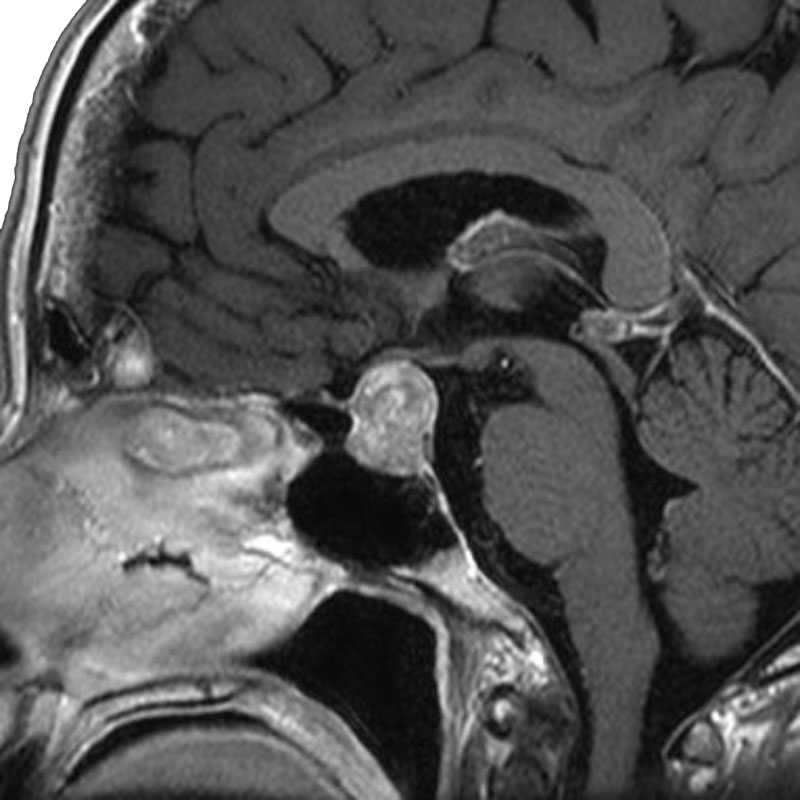

脳動静脈奇形

血管塞栓術

松田/濵田/元永